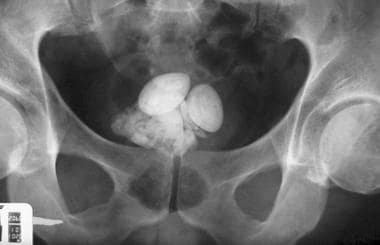

요로결석은 소변이 만들어져 배출되는 길인 요로에 결석이 생기는 질환입니다. 결석은 주로 칼슘, 수산염, 인산염 등의 무기질이 소변에 녹지 못하고 결정으로 뭉쳐져 생성됩니다.

요로결석은 신장, 요관, 방광, 요도 등 어디에서나 생길 수 있지만, 가장 흔하게는 요관에서 생깁니다. 요관은 신장에서 방광으로 소변을 운반하는 관으로, 지름이 약 5mm 정도입니다. 결석이 요관에 생기면 통증, 구역질, 구토, 혈뇨 등의 증상이 나타날 수 있습니다.